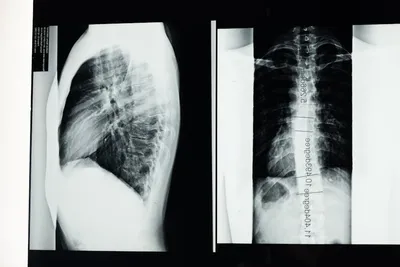

noun Скачать 🔗Поделиться Сколиоз A condition in which there is abnormal lateral curvature of the spine. Examples : "After a medical examination, the doctor told Sarah that she had scoliosis, explaining that it was a sideways curve in her spine. " После медицинского осмотра врач сообщил Саре, что у нее сколиоз, объяснив, что это боковой изгиб позвоночника. medicine anatomy body disease condition Чат с ИИИгра со словамиПрактика чтения